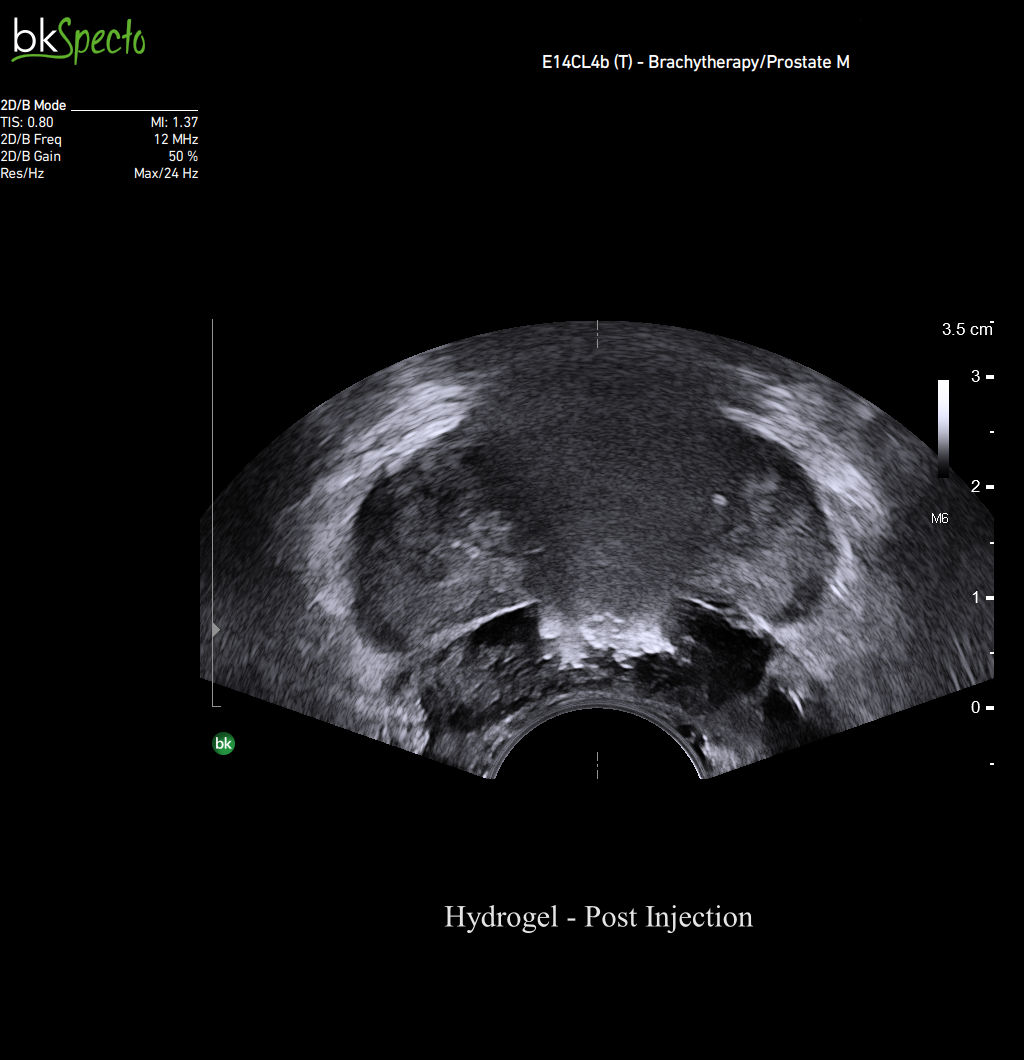

Hydrogel rectal spacer placement

When your target is small, excellent imaging is vital. Our advanced imaging technology allows you to visualize the critical perirectal space and needle path with precision. By using simultaneous imaging of transverse and sagittal planes, you can clearly see the separation of the rectal wall and prostate. Additionally, you can view injections in real-time, enhancing accuracy and confidence during procedures.